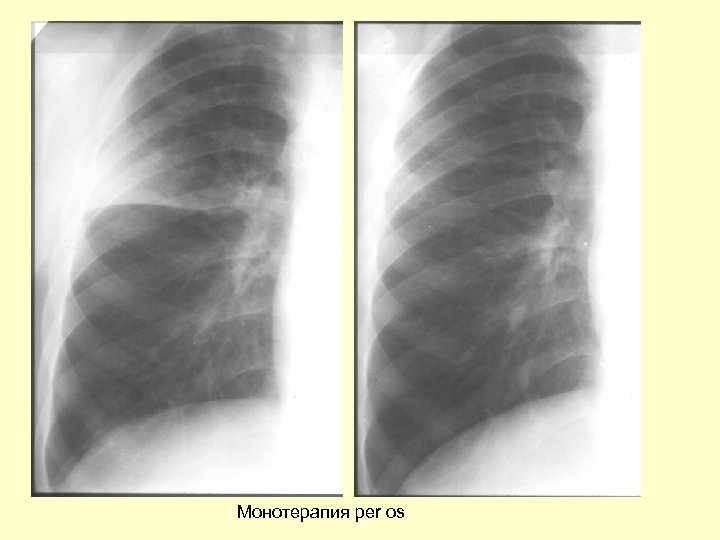

Монотерапия per os